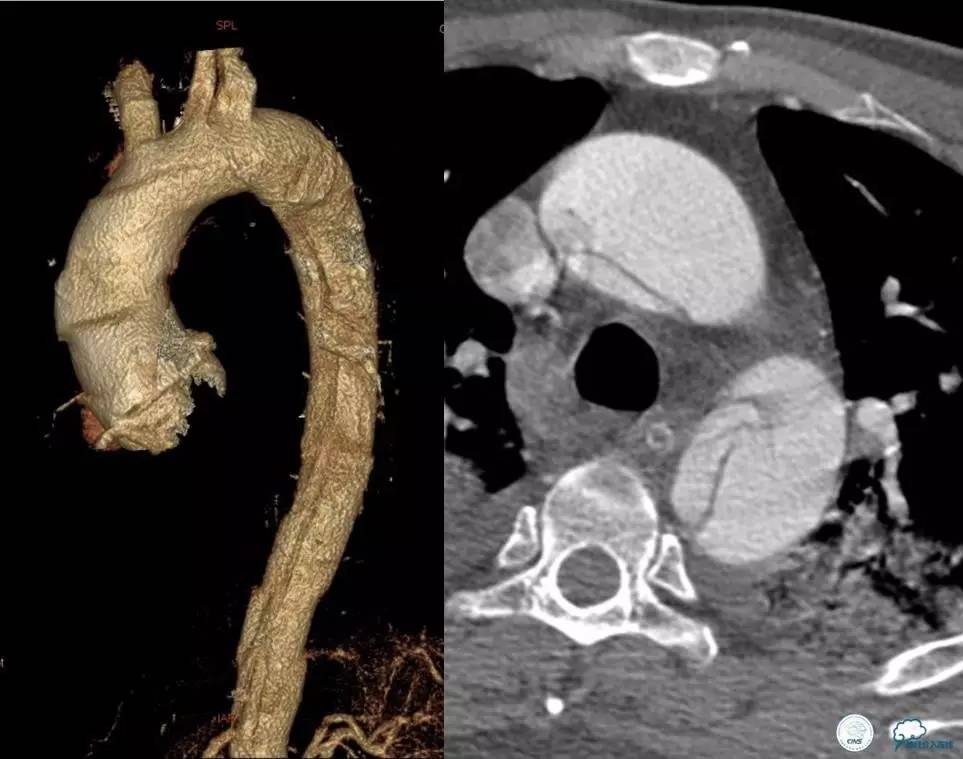

▼主动脉全程CT

诊断:

主动脉夹层 DeBakey Ⅰ型

短暂性脑缺血发作

急性心肌缺血

急性肾功能不全

急性肠系膜动脉缺血

处理意见:

继续监测血流动力学指标

绝对卧床、强效镇静与镇痛

急请血管外科会诊